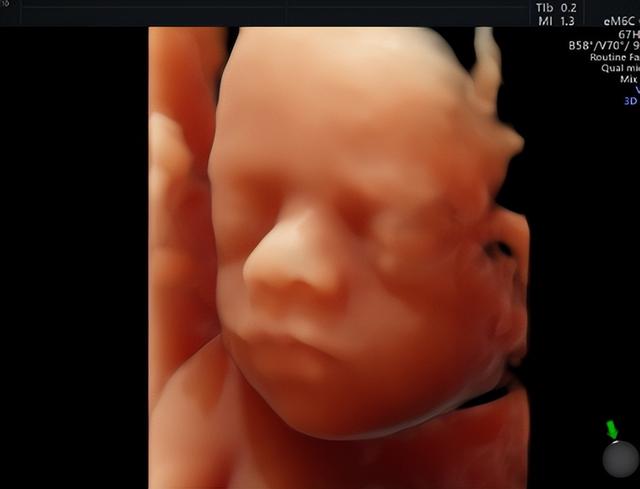

四维彩超还有一个名字“宝宝的0岁写真”。相比三维彩超,四维彩超更形象、更立体、更动态。

筛查胎儿畸形,检查宝宝在子宫内的发育情况,是否符合孕周,四肢、颜面部、内脏有无畸形,以及羊水、脐带情况。因此,在合适的时候做四维彩超是非常有必要的。

从医学角度来说,做四维检查可以全面、多维度的观察胎儿的发育情况,能够检查胎儿的面部、脊柱、神经系统、泌尿系统、消化系统、心脏是否健康。

医生通过细致的观察,为早期诊断胎儿先天性畸形和先天性心脏疾病提供准确的科学依据。

湖南妇女儿童医院引进多台美国GE系列机器,满足从早孕期到孕晚期的全程早期检查和诊断,在四维检查中成像高清、立体,大大提升了临床检查和诊疗的准确度。